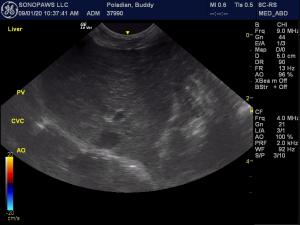

Abdo u/s for diarrhea.

5mm stone/sand in bladder, kidneys normal size (3cm), small right adrenal 2.8mm (artifact vs atypical Addison), intestines: speckles in mucosa (IBD, food sensitivity or incidental), normal LN, normal pancreas, no ascites.

Liver: normal size, but the PV looks smaller than CVC and Aorta at the hilus. Torb given for the scan. No dilated hepatic veins.

I realized the PV was small once I was home! I did not do a shunt hunt bc the liver had a good size…

Can we blame the large CVC/aorta on the DCM? Or is my angle off?

The portal vein looks fine on the view with the pylorus.

In your first pv video with the cvc you are imaging a branch of the pv. To compare pv cvc ratio properly you have to have them paralell to each other see images attached here. Also can’t use dexdom or similar as that dilated the cvc. Also heavy manual pressure will collapse veins so have to get into the portal hilus then let up on pressure. Your images all appear normal to me with regards to the angle and approach. SDEP 13 and SDEP 14, 1 second into the C-loop puts you in perfect shunt hunt pv cvc ratio position.